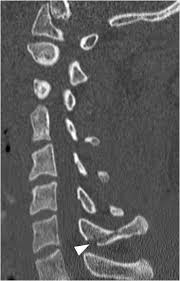

A transverse process fracture at the level of l5 is a surrogate marker of vertical instability of the pelvic fracture due to the attachment of the iliolumbar ligaments. Possible causes, signs and symptoms, standard treatment options and means of care and support. Transverse processes are used as lever arms by the deep spinal muscles to maintain posture and to induce rotation and lateral bending. It may occur as an avulsion fracture due to strong contracture of the muscles. Although the fracture is not associated with spinal cord damage and neurological deficits, the extreme force of the injury can cause visceral injuries and internal hemorrhage. The presence of other injuries might also be assessed due to the level of force needed to break the transverse process. In 78% of transverse process fractures, ct scanning showed that the fracture extended into the transverse foramen. Transverse process fractures caused by stress are likely under detected since even an acute transverse process fracture requires a high index of suspicion to be correctly identified(4,7). Here is an example of a patient with a benign looking transverse process fracture with an associated significant injury to the back. Transverse process fracture you have fractured a transverse process. Thoracic transverse process fractures (ttpfs) are injuries that go unnoticed during traditional autopsies, as demonstrated by a lack of medicolegal publications regarding ttpfs. We retrospectively reviewed the reports of lumbar spine and abdominopelvic ct scans from 2017 and 2018 to classify the types of spine fractures, their mechanism of injury, treatment and. Up to 60% of lumbar transverse process fractures identified on ct will be missed on plain radiographs.

The transverse foramen is an opening on each of the transverse processes of the cervical spine which gives passage to the vertebral artery and vein and a sympathetic nerve plexus. There are two transverse processes that extend off each vertebra in the details: Transverse process fractures are common sequelae of trauma, although they are considered a minor and stable lumbar spine fracture. Transverse processes are typically fractured in direct blows from athletics touch or impact from falls from bikes/motorbikes or by heights. However, postmortem computed tomography (pmct) has made detection of this type of injury easy. There are two transverse processes that extend off each vertebra in the spine, one on each side. A transverse process fracture is a break in 1 or more transverse process. In 78% of transverse process fractures, ct scanning showed that the fracture extended into the transverse foramen. A transverse process fracture is considered as a rare injury. A transverse process fracture is a break in 1 or more transverse process. What is a transverse process fracture? Transverse process fractures caused by stress are likely under detected since even an acute transverse process fracture requires a high index of suspicion to be correctly identified(4,7). If ct confirms isolated injury lateral flexion/extension views are indicated to rule out dynamic instability.

However, postmortem computed tomography (pmct) has made detection of this type of injury easy. There are two transverse processes that extend off each vertebra in the details: What is a transverse process fracture? It may occur as an avulsion fracture due to strong contracture of the muscles. It occurs as a result of sudden and extreme trauma. If ct confirms isolated injury lateral flexion/extension views are indicated to rule out dynamic instability. Vertebral angiography, performed in eight patients with fractures involving the transverse foramen, showed dissection or occlusion of the vertebral artery in seven (88%) instances. This part extends out from the side of the main body of the bone (called the vertebral body). A transverse process fracture at the level of l5 is a surrogate marker of vertical instability of the pelvic fracture due to the attachment of the iliolumbar ligaments. We retrospectively reviewed the reports of lumbar spine and abdominopelvic ct scans from 2017 and 2018 to classify the types of spine fractures, their mechanism of injury, treatment and. Up to 60% of lumbar transverse process fractures identified on ct will be missed on plain radiographs. In 78% of transverse process fractures, ct scanning showed that the fracture extended into the transverse foramen. Transverse process fractures identified on helical computed tomography (ct) scans without the presence of any other fracture or.